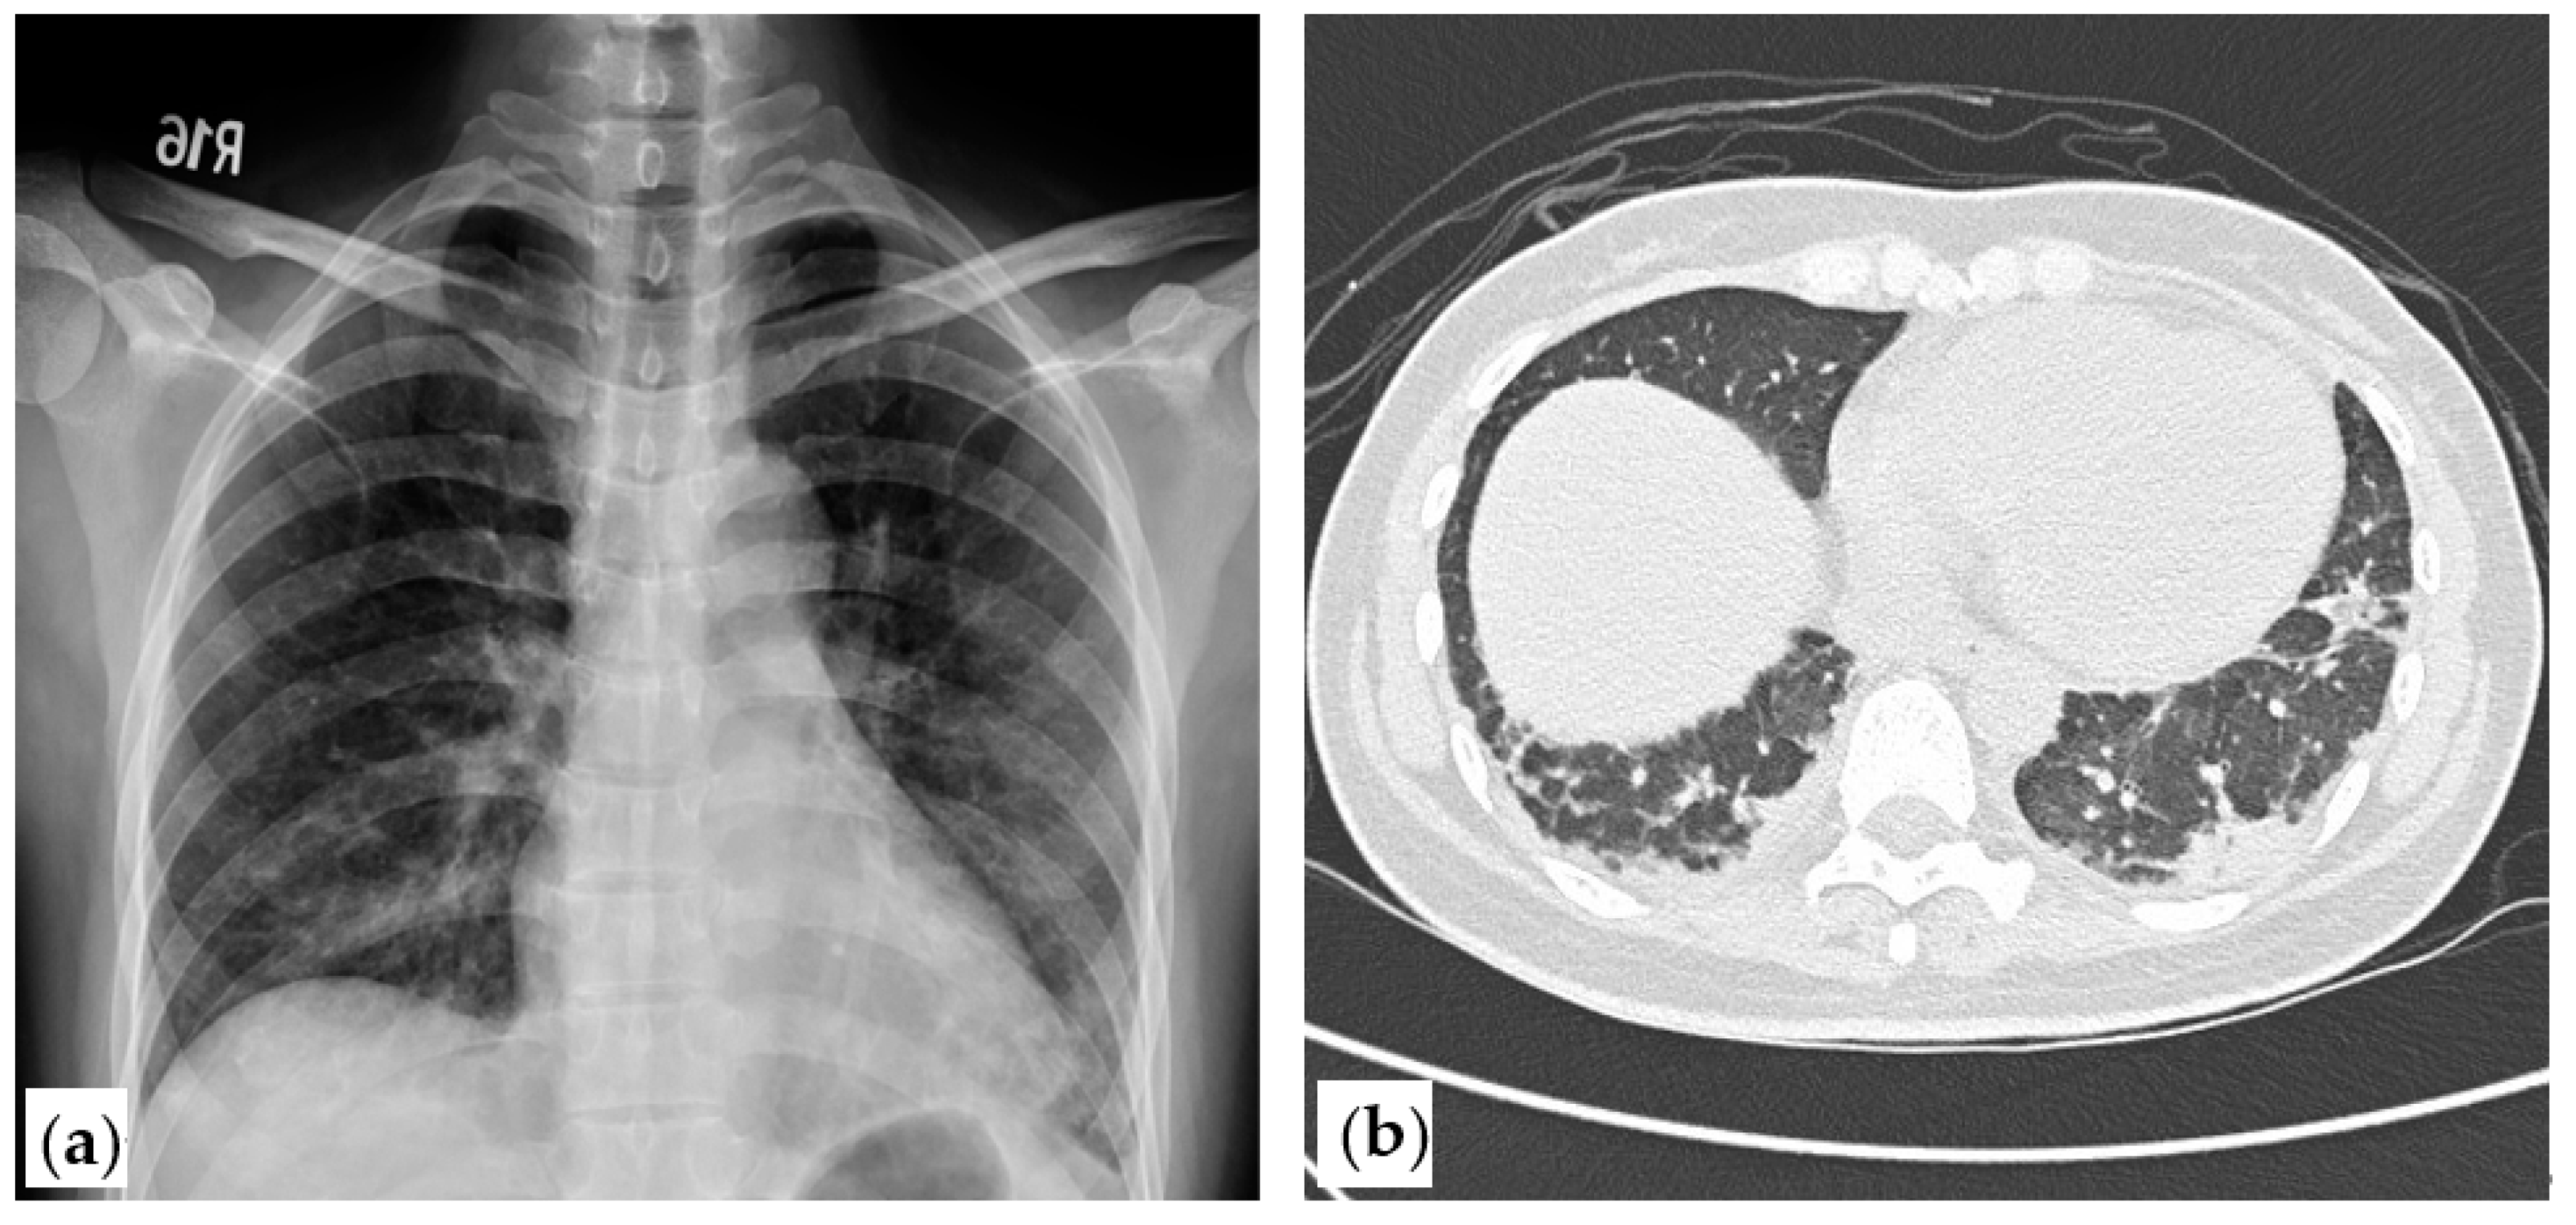

2. Case Presentation